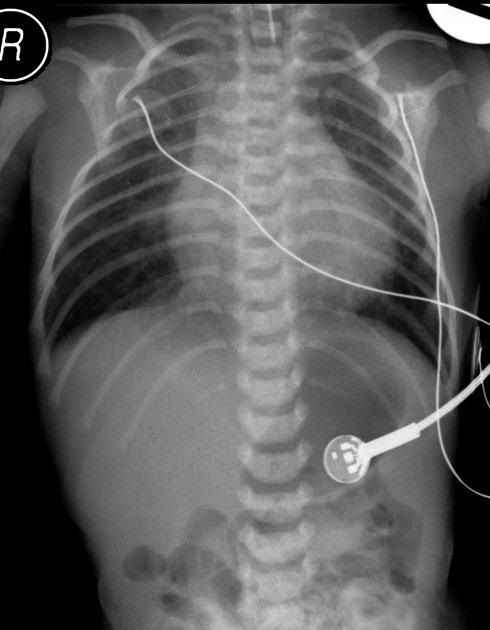

First image - antero-posterior thoraco-abdominal x-ray; Second image - Latero-lateral thoraco-abdominal x-ray; Both images with intestinal aeration suddenly interrupted in the middle abdominal floor; opacity in the lower abdominal floor |

Early-onset neonatal sepsis associated with ileal atresia (Romania)

Clinical Area: Infectious diseases

We report the case of a term newborn female, small for gestational age, born at a gestational age of 38 week and 3 days in our 3rd level maternity. The anamnesis pointed out that he originated from an unmonitored pregnancy. At admission, she presented grunting, oxygen saturations 80% in ambient air ...